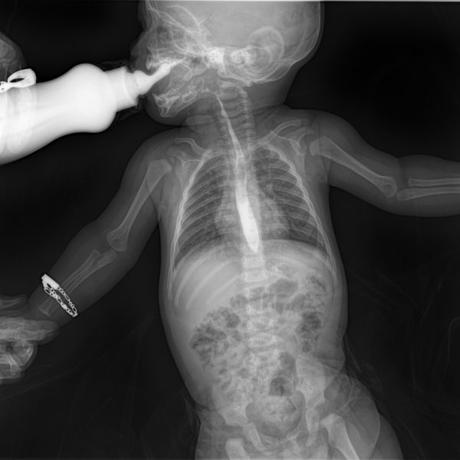

ESTUDIO SOLICITADO: SERIE ESOFAGOGASTRODUODENAL.

Se realiza Esofagograma con material de contraste baritado, por vía oral y por medio de control fluoroscópico se toman distintas proyecciones observando lo siguiente.

Se observa mecánica de la deglución con adecuado paso de medio de contraste de faringe a esófago sin presencia de defectos de llenado depósitos anómalos o fuga del mismo.

ESÓFAGO se observa de situación, calibre y trayecto normal. Contornos regulares y bien definidos. No se observan depósitos anómalos, defectos de llenado o fuga del medio de contraste.

UNION ESOFAGOGASTRICA se observa con calibre y situación normal. Sin observar reflujo a las maniobras de valsalva

ESTOMAGO se observa en su situación habitual, distendido, sin defectos de llenado.

- Actualmente no se demuestra Reflujo gastro-esofágico.

- Estudio de apariencia normal.